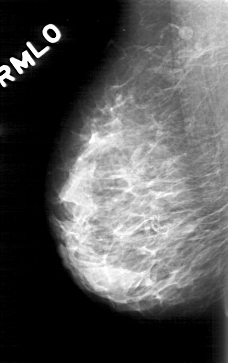

D_4171_1.RIGHT_MLO

RIGHT_MLO LINES 5071 PIXELS_PER_LINE 3181 BITS_PER_PIXEL 12 RESOLUTION 43.5 NON_OVERLAY

ABNORMALITY 1

LESION_TYPE CALCIFICATION TYPE ROUND_AND_REGULAR-PLEOMORPHIC DISTRIBUTION CLUSTERED

ASSESSMENT 0

SUBTLETY 3

PATHOLOGY BENIGN